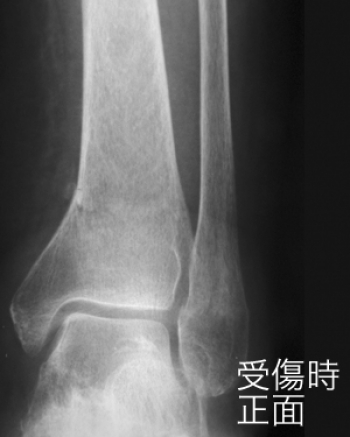

º£Æü¡¢¤´¾Ò²ð¤¹¤ë¤Î¤Ï¡¢²¼Âܱó°ÌüÉô¹üÀޤˤĤ¤¤Æ¤´¾Ò²ð¤·¤Æ¤¤¤­¤Þ¤¹¡£

²¼Âܹü±ó°ÌüÉô¹üÀÞ

­´ØÀáÉô¤Î¹üÀޤϡ¢¤È¤¯¤Ë¥¹¥Ý¡¼¥Ä³°½ý¤Ç¿ȯ¤·¤Þ¤¹¡£

²ò˶³ØÅª¾õÂ֤ؤβóÉü¤Ë¼ºÇÔ¤¹¤ë¤È¡¢Â­´ØÀá¤ÎưÍÉÀ­¤ä¡¢ÊÑ·ÁÀ­´ØÀá¾É¤ò»Ä¤·¡¢µ¡Ç½¾ã³²¤òÀ¸¤º¤ë¤³¤È¤â¤¢¤ë¡£

²¼Âܹü¹ü´´Éô¹üÀÞ¤ÎʬÎà

­¡³°Å¾·¿¹üÀÞ¡ÊPott¹üÀÞ¤Þ¤¿¤ÏDupuytren¹üÀÞ¡Ë

­¢»°²ÌÉô¹üÀÞ¡Ê¥³¥Ã¥È¥ó¹üÀÞ¡Ë

­£Æâž·¿¹üÀÞ

³°Å¾·¿¹üÀÞ

¤â¤Ã¤È¤â¤ß¤é¤ì¤ë²ÌÉô¹üÀޤϡ¢Â­´ØÀá¤Î³°Å¾¶¯À©¤Ë¤è¤Ã¤Æµ÷¹ü¤¬¼Ð°Ì¤È¤Ê¤ê¡¢Â­´ØÀáÆâ¦¤Î¿ÙÂÓ¤¬¶ÛÄ¥¤·¤ÆÃÇÎö¤·¡¢¤Þ¤¿¤Ï¿ÙÂÓ¤¬ÃÇÎö¤·¤Ê¤¤¤ÇÆâ²Ì¤ÎÇíÎ¥¹üÀÞ¤òÀ¸¤¸¤ë¡£